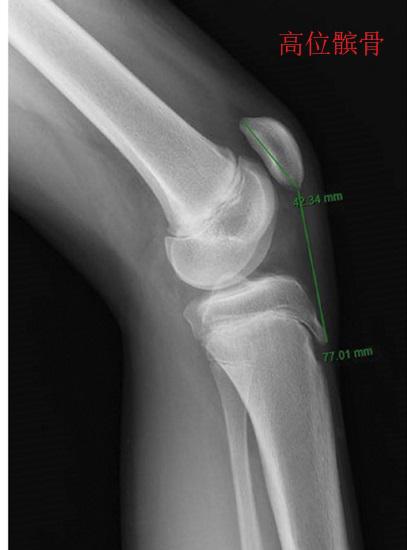

股四头肌收缩和髌骨推移 若存在低位髌骨、髌腱挛缩、股四头肌萎缩的现象,可在仰卧姿或站姿状态下主动收缩股四头肌,以获得牵拉髌腱、激活股四头肌力量的作用。在临床上,也有人通过髌骨手法推移(向近端推移)的方法达到牵拉髌腱的目的,但有研究显示实际效果微乎其微。